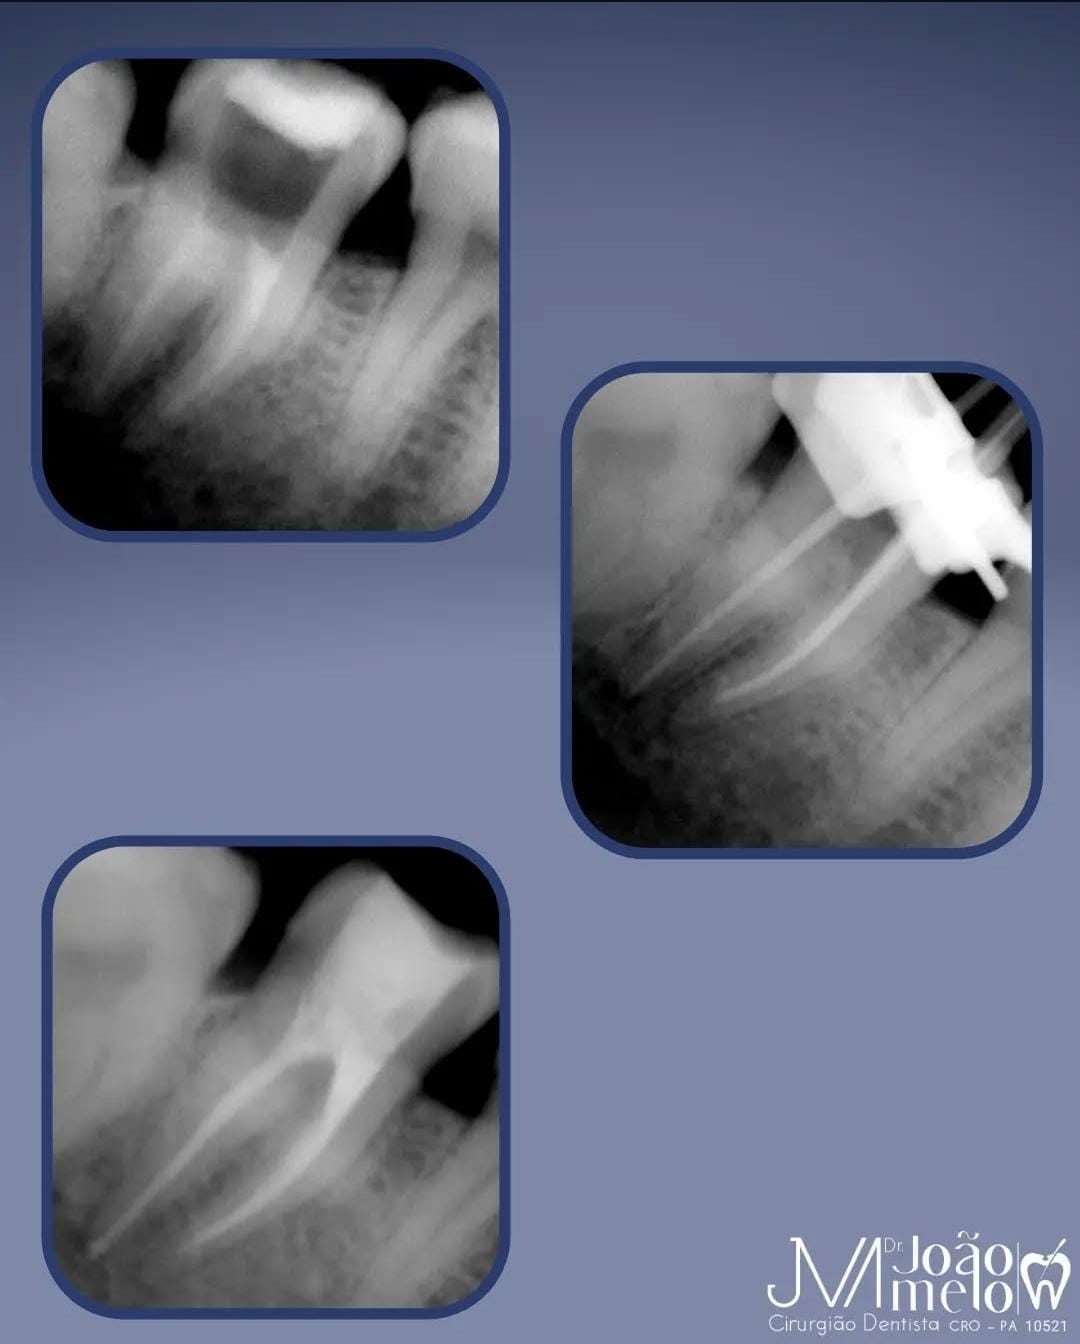

Post 1

Post 2

Post 3

Post 4

Post 5

Post 6